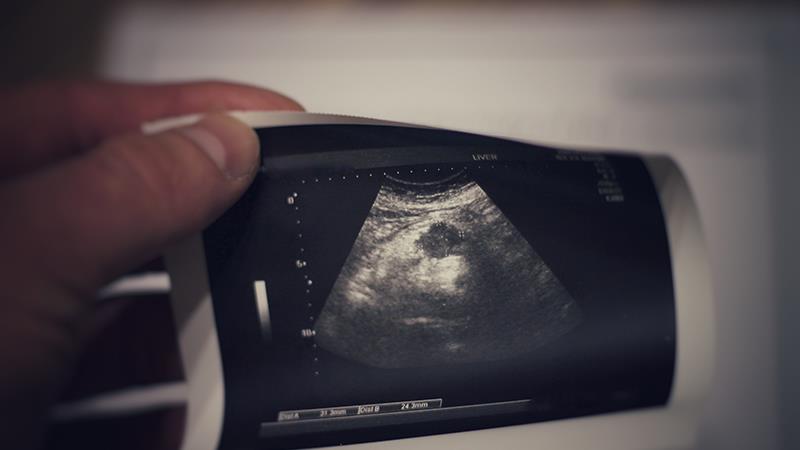

“Unfortunately, these symptoms often present late and curative treatments are not feasible on diagnosis,” said Yoong. However, for those detected during screening as indicated by raised CA19-9 in the blood test or pancreatic mass on ultrasound, surgical removal of the tumour is the only chance of cure. Those detected with precancerous tumours have the best prognosis and surgical resection would usually cure them. Hence, those who experience the signs of pancreatic cancer should be advised to go for screening as soon as possible, he added.